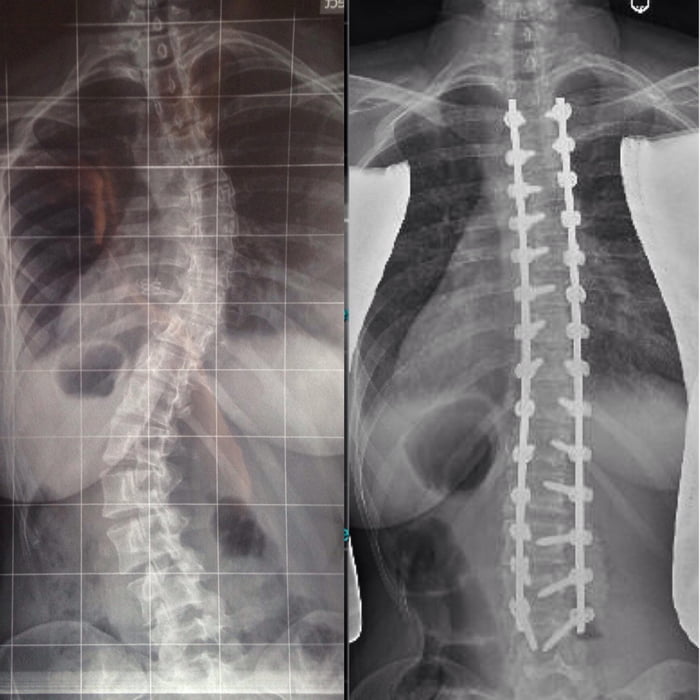

Медицинские снимки: рентген позвоночника сбоку